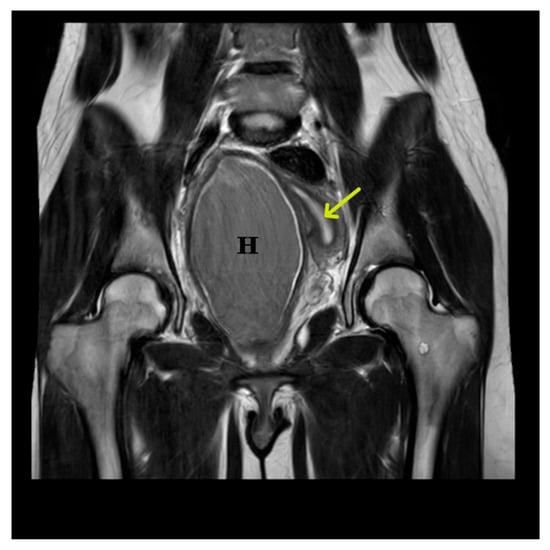

2. Case Presentation